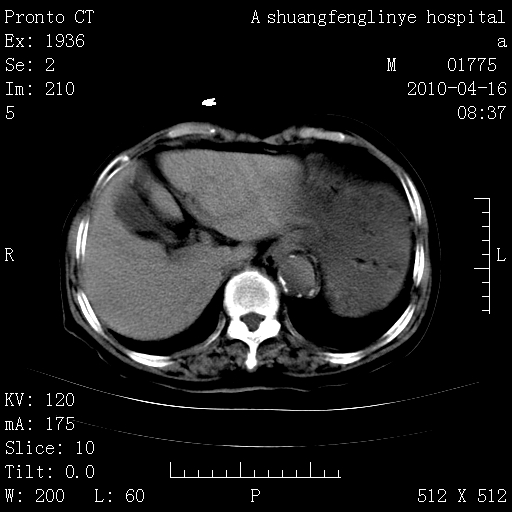

陈旧性结核,胃腔扩大,脾脏受压后移

典型 夹层动脉瘤。 内膜瓣钙化移位

1)左肺上叶结核(纤维、增殖病灶)。2)冠状动脉及主动脉钙化。肺动脉高压